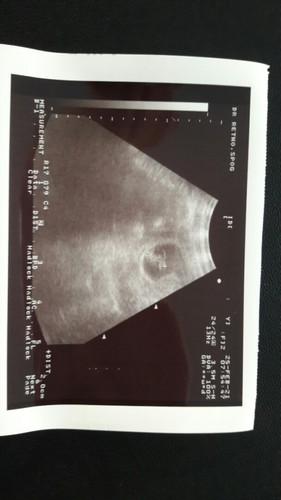

Bund, ini hasil USG 9weeks. Kata dokter sdh ada janin, tapi denyutnya tdk teraba. Dicoba pertahankan 1minggu dulu, kalau tdk ada perkembangan disarankan curet. 😭😭 Apa memang tdk ada denyut itu tdk normal ya bund? Atau ada bunda yg mengalami hal yg sama, mungkin bisa sharing2 biar sedikit tenang. #seriusnanya #bantusharing #ingintahu #firstbaby